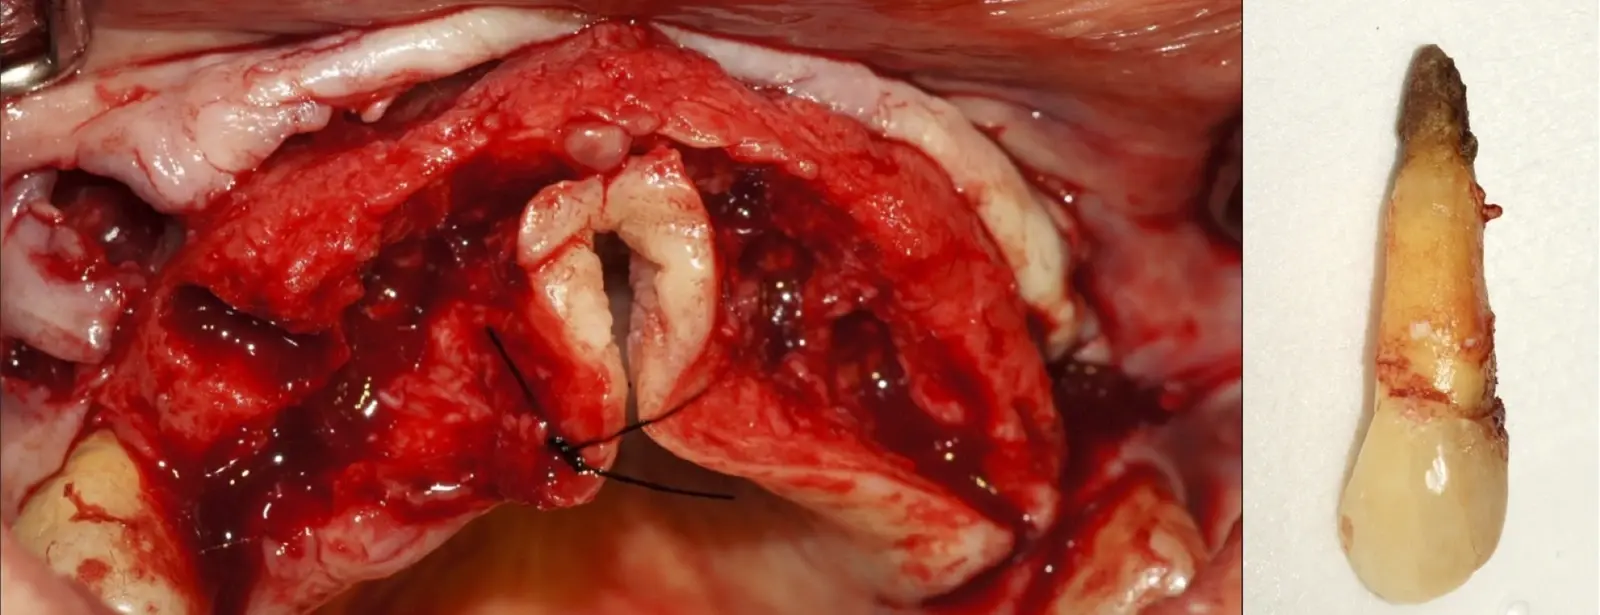

El procedimiento se inicia colocando anestesia y elevando un colgajo mucoperióstico a espesor completo y exponiendo la zona. En seguida se realiza la enucleación de la lesión, eliminando o creando una ventana en la lámina cortical que contiene el área del ápice.

El procedimiento se inicia colocando anestesia y elevando un colgajo mucoperióstico a espesor completo3 (incisión semilunar o intrasurcular con/sin protección papilar) y exponiendo la zona. En seguida se realiza la enucleación de la lesión, eliminando16 o creando una ventana17 en la lámina cortical que contiene el área del ápice; este retiro óseo se realiza con los insertos de forma aplanada dentada o inserto con cobertura diamantada plano o redondo, recordando ser lo más conservador posible (Figura 5).

Después de realizado el acceso e identificado el ápice, se procede a la limpieza de la zona con instrumentos manuales y/o con insertos diamantados de parte activa angulada para poder eliminar todo el tejido patológico del perímetro radicular apical y del tejido óseo circundante (Figura 6).

Para la obturación retrograda, el sellador más usado es el agregado de trióxido mineral (MTA)21 por sus propiedades hidrofílicas y de biocompatibilidad que favorece la neoformación ósea.3 Luego de la desinfección y secado, se realiza la obturación-compactación de rutina y se culmina con la reposición de los tejidos gingivales a través de puntos de sutura (Figura 10).